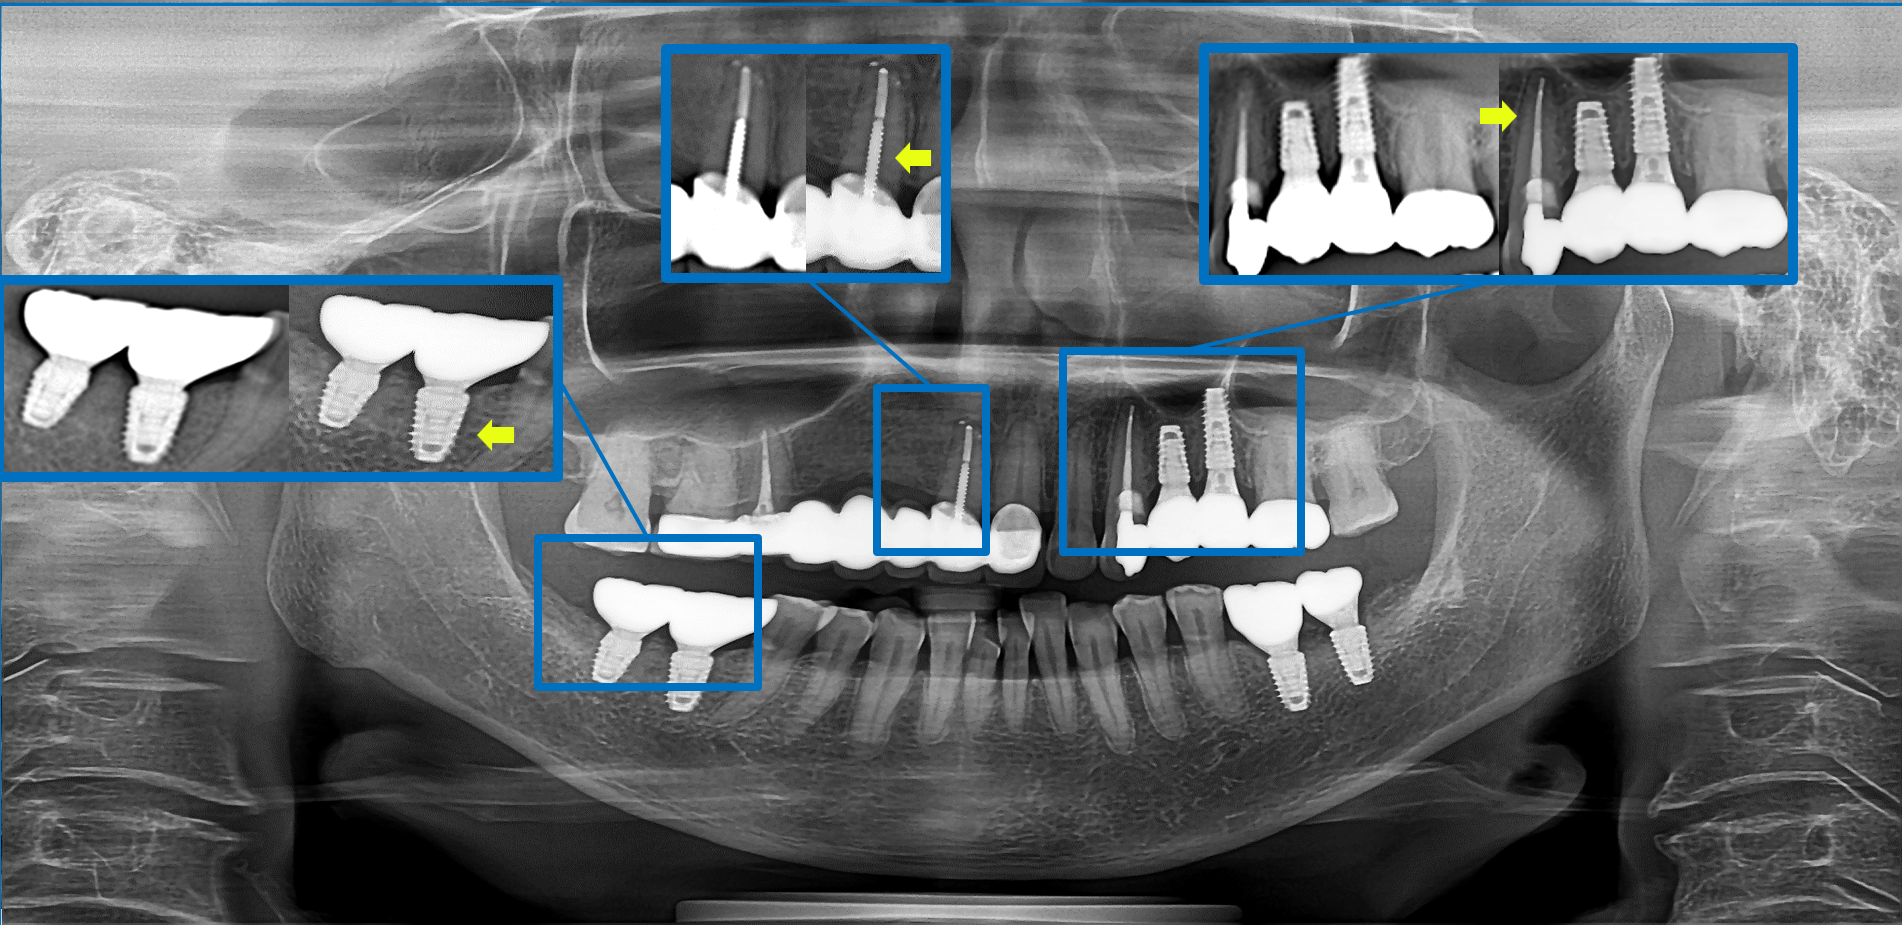

Tehnologia MAR Plus – Reducerea Artefactelor Metalice

Dentium MAR (Metal Artifact Reduction) reduce automat artefactele metalice cauzate de implanturi, obturații sau restaurări, asigurând imagini clare și precise. Aceasta contribuie la confirmarea diagnosticului și minimizează riscul de interpretare greșită.